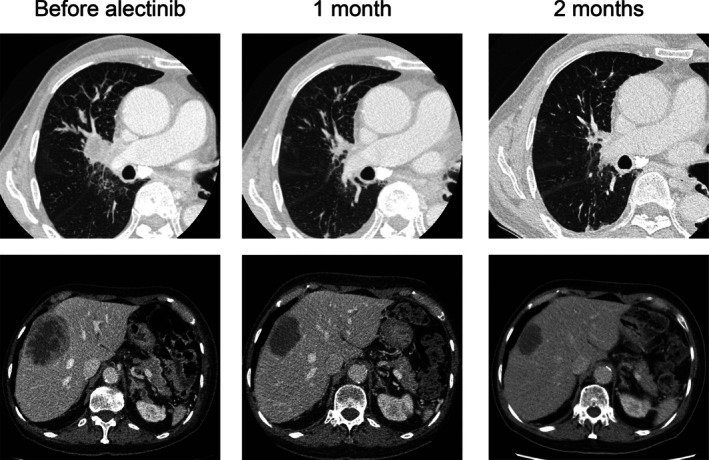

ALK融合是肺癌中公认的致癌驱动因素,通常通过伴侣蛋白介导的二聚化导致ALK活化。然而,ALK活化的其他机制也有报道。我们在此报告一位80岁的男性转移性肺腺癌患者,他最初使用基于聚合酶链反应的检测结果为ALK重排阴性。基于rna的杂交捕获靶向测序随后鉴定了EML4-ALK融合转录物,其中EML4外显子15和ALK内含子19融合在一起。这导致停止密码子保留在未剪接的ALK内含子19中,阻止融合蛋白翻译。然而,免疫组织化学显示ALK过表达,提示在20外显子或下游存在替代翻译起始位点。患者对阿勒替尼治疗有明显反应。这个病例强调了使用多种方法来检测可操作的基因融合和确保适当的靶向治疗选择的重要性。

ALK fusions are well-established oncogenic drivers in lung cancer, typically resulting in ALK activation through dimerization mediated by partner proteins. However, alternative mechanisms of ALK activation have also been reported. We herein report an 80-year-old man with metastatic lung adenocarcinoma, who initially tested negative for ALK rearrangement using a polymerase chain reaction-based assay. RNA-based hybrid capture targeted sequencing later identified an EML4-ALK fusion transcript in which EML4 exon 15 and ALK intron 19 were fused. This resulted in a stop codon being retained in the unspliced ALK intron 19, preventing fusion protein translation. However, immunohistochemistry revealed overexpression of ALK, suggesting the existence of alternative translation initiation sites in exon 20 or downstream. The patient showed a marked response to alectinib therapy. This case underscores the importance of using multiple methods to detect actionable gene fusions and to ensure appropriate targeted therapy selection.